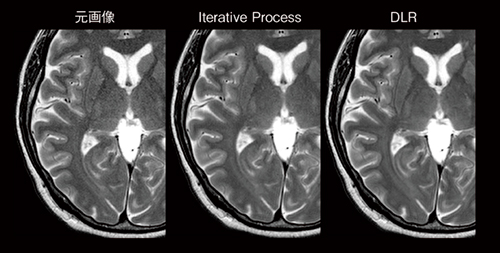

3.短いスキャン時間でも高画質な画像を取得できる画像処理技術

MR画像のスキャン時間と画質はトレードオフの関係にあり,高画質な画像を得るためにはスキャン時間を長くする必要があります。ECHELON Synergyは,繰り返し演算処理を行う独自の高速撮像法「IP-RAPID」と,AI技術を活用して新たに開発したノイズ除去技術「Synergy DLR」を組み合わせることで,より短時間で高画質な画像の取得が期待できます(図5,6)。

Synergy DLRは,すべての2Dのシーケンスおよび3Dのシーケンスに適用することが可能です。また,静音化機能「Soft Sound」を併用することで被検者のストレスを軽減して動きを抑え,アーチファクトを抑制した画像を得ることが可能になります。

図5 IP-RAPIDとSynergy DLRを組み合わせた画像処理技術

繰り返し演算処理を行う独自の高速撮像法IP-RAPIDと,AI技術を活用して新たに開発したノイズ除去技術Synergy DLRを組み合わせることで,より短時間で高画質な画像の取得が期待できる。

図6 元画像,Iterative Process,DLRの画像比較